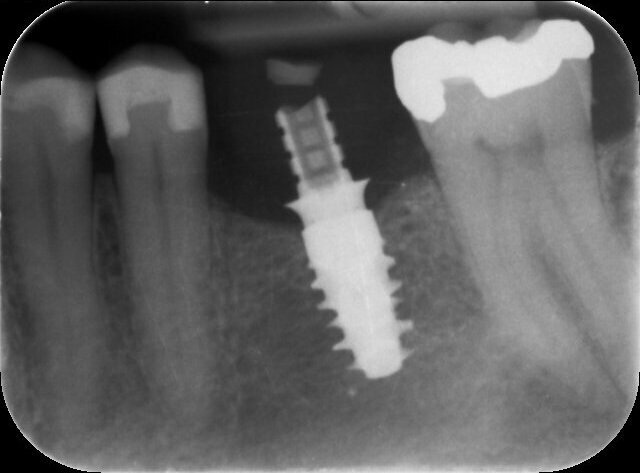

The patient, a 67-year-old non-smoking man without any relevant medical history, was referred to the office with a missing tooth (#36) due to persistent apical periodontitis. The tooth had been extracted more than one year prior to the procedure and the molar site was well maintained and fully healed (Fig. 1). A CBCT scan showed that the patient had favourable bone availability (Fig. 2), on which basis a one-stage placement of a 5.5 × 10.0 mm Straumann BLX implant was planned. After surgically installing the implant (Figs. 3–7), Salvesen allowed the surrounding soft tissue to mature and heal for six weeks (Fig. 8). He then removed the healing abutment to begin the prosthetic procedures for a temporary crown (Figs. 9 & 10). A stone master cast was made in the laboratory, and a temporary screw-retained PMMA crown was manufactured over a Straumann wide base temporary abutment for the crown (Fig. 11) and placed on to the implant (Figs. 12–14).

After 12 weeks, Salvesen removed the temporary crown, revealing that the soft tissue had healed very well (Fig. 15). He then began the digital workflow. For the final crown, a digital impression was taken with a 3Shape intra-oral scanner, using a Straumann CARES scan body. A monolithic zirconia crown was then seated passively on to the implant in a healed and preconditioned soft-tissue environment (Figs. 16–19).